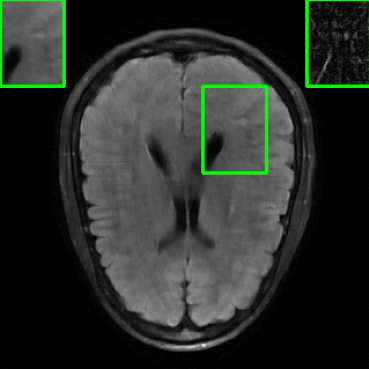

Performance on Data with Lesions: While the previous experiment allowed comparing reconstruction quality with or without planted features, here we test our method on MRI scans with lesions, which are often regions of abnormal or diseased tissue. We utilize the annotated fastMRI+ data666https://github.com/microsoft/fastmri-plus/tree/main to evaluate our method’s image reconstruction capabilities, and compare its outcomes with established baselines. For the training phase, the non-lesion dataset was employed for the global training approach with images whereas LONDN-MRI used adaptively selected images for training (searched from images). In contrast, during the testing phase, we used scans with lesions. The results, as displayed in Table V, indicate that our method achieves substantially higher PSNR values in comparison to the globally trained baseline as well as the LORAKI method. Furthermore, visualizations in Figure 16 clearly demonstrate the superiority of our method, particularly in the nonspecific white matter lesion areas. Thus, both in terms of visual assessment and PSNR values, our approach outperforms the existing baselines and aligns more closely with the ground truth.

| Ground Truth | LORAKI | Global | LONDN-MRI | LONDN-MRI | Oracle |

| (1 iteration) | (2 iterations) | ||||

![]() |

| PSNR = dB | PSNR = 31.45 dB | PSNR = 32.15 dB | PSNR = 32.72 dB | PSNR = 33.15 dB | PSNR = 33.22 dB |